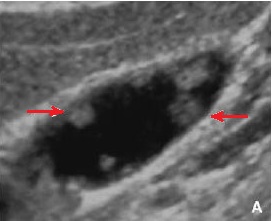

Image echographique en coupe

longitudinale de la vesicule biliaire : Aspect de

multiple formation polypoide adenomateuse

isoechogene de type pedicule ( fleche rouge ) . |

Image echographique d'une polyp

adenomateuse de type sessile supracentimetrique (

fleche rouge ) |